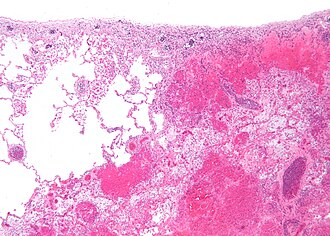

Template:Px Pulmonary infarct. H&E stain. | |

| LM | necrosis of alveolar walls - loss of nuclei, alveolar hemorrhage, +/-evidence of underlying cause |

- Necrosis of alveolar walls - loss of nuclei.

- Alveolar hemorrhage.

Pulmonary infarct - low mag. (WC)